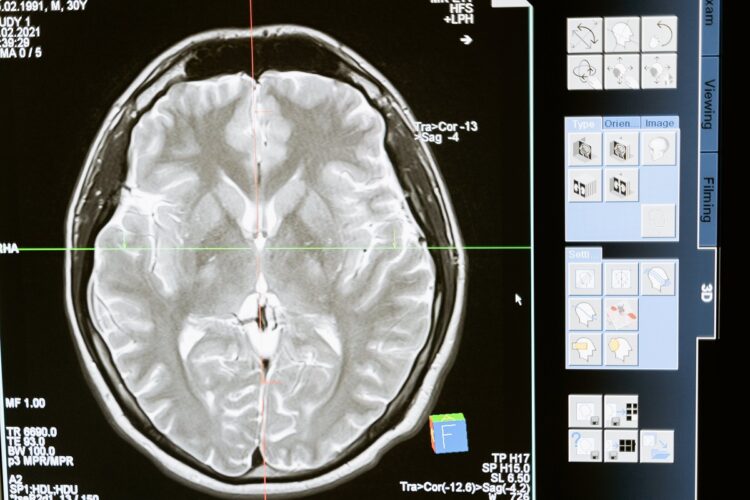

O que é um AVC isquémico?

O AVC isquémico ocorre quando o fluxo de sangue no cérebro é reduzido ou interrompido, afetando as células cerebrais, que deixam de funcionar normalmente por causa da falta de oxigénio e de nutrientes.